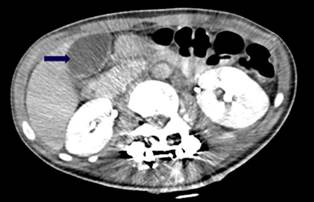

La paciente inicialmente no mejora con el tratamiento administrado, continuando con dolor abdominal intenso y deterioro clínico, por lo cual se decide realizar tomografía de abdomen contrastada con evidencia cambios de patología vesicular correspondientes a adenomiomatosis, con líquido perivesicular asociado e íleo intestinal (Figura 2). Ante el deterioro imagenológico a nivel vesicular, se consideró que la paciente reunía las condiciones para ser llevada a cirugía laparoscópica, en la que se encontró una vesícula de paredes gruesas con presencia de material purulento (piocolecisto) con la vesícula adherida al duodeno.

Fuente: historia clínica del paciente.

Figura 2 Tomografía axial computarizada (TAC) de abdomen contrastado. La flecha indica persistencia de hallazgos compatibles con adenomiomatosis vesicular, un discreto aumento del diámetro anteroposterior de la cola y grasa peripancreática conservada con aumento perivesicular.